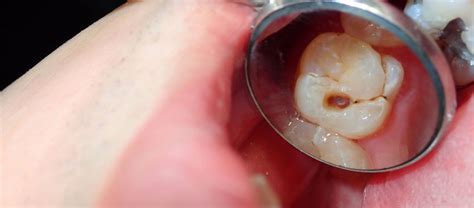

La muela picada es un problema dental común que afecta a personas de todas las edades. Una muela picada, también conocida como caries dental, es una afección muy común que se produce cuando las bacterias presentes en la boca descomponen el esmalte de los dientes, creando pequeñas cavidades o agujeros. Estas cavidades, si no se tratan a tiempo, pueden llegar a afectar la dentina y la pulpa dental, las capas internas del diente. Esta afección, también conocida como caries dental, se manifiesta en forma de pequeños agujeros que aparecen en las capas exteriores de los dientes, llamadas esmalte y dentina, y que protegen la pulpa dental.

- Manchas en los dientes: Las caries pueden causar manchas blancas, marrones o negras en la superficie del diente, especialmente en las zonas afectadas.